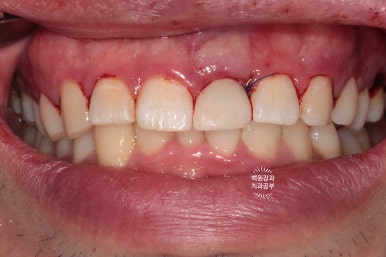

환자분은 왼쪽 상태로 귀가하실 수 있었습니다.

전후 비교를 해보면~~

위처럼 뿌리만 있었던 치아를 제거하고,

발치 즉시 임플란트를 시행 후 뼈이식과 임시치아 연결을 통해

아래처럼 귀가하실 수 있게 되었던 것입니다.

모두가 다 하루에 가능한 임플란트 수술과정이었습니다.

비록 임시치아는 레진 치아라 다소 어색함이 있을 수 있으나,

환자분께서 매우 만족해하셨습니다.

열흘 지나 실밥을 제거했을 때 보니 함께 시행했던 잇몸치료를 통해,

coral pink color를 회복한 건강한 잇몸과 보다 더 조화로워진 앞니를 볼 수 있었습니다.

생각보다 자연스러운 색의 치아와 (white esthetic) 잇몸의 색깔을 보실 수 있습니다. (pink esthetic)

옆에서 보면 왠지 치아 주변이 조금 검은듯한 느낌이 들기는 하나,

바로 옆에 위치한 또다른 가운제 앞니와 비교했을 때 큰 차이 없이 적절한 외형의 임플란트 보철물을 보실 수 있어요.

앞에서 볼 땐 꽤나 자연스러운데,